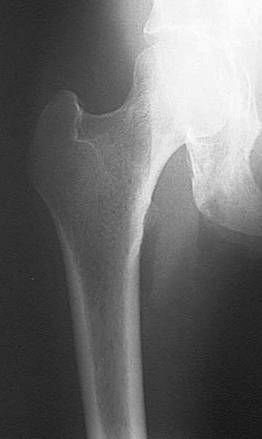

Radiografia articulatiei coxo-femurale - A-P

Pacientul in DD; membrele inferioare in extensie si lipite; calcaiele departate, varfurile apropiate.

RC perpendiculara pe caseta, intra la doua laturi de deget sub mijlocul liniei care uneste spina iliaca antero-superioara cu pubisul. Film de 24x30 cm, in lung; marginea proximala a casetei la un lat de deget deasupra spinei iliace antero-superioare; marginea laterala depaseste cu trei laturi de deget partile moi.

Distanta F-F = 1m; cu Bk.